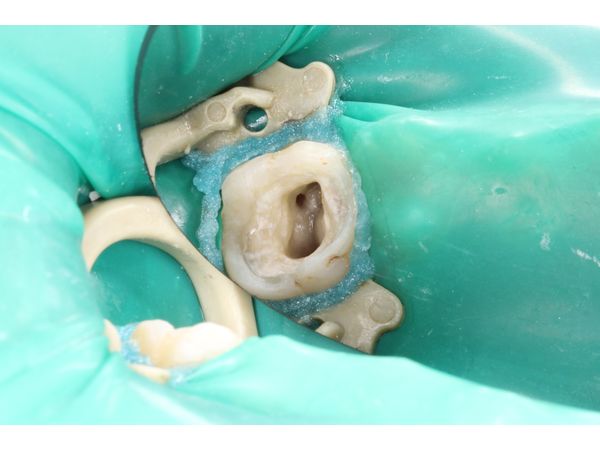

- сделали инфильтрационную анестезию Ультракаином Д-С (1,7 мл) и изолировали рабочее поле латексным платком;

- под воздушно-водяным охлаждением убрали старую пломбу и кариес с помощью наконечника и бора, после чего удалили пульпу и создали доступ к устьям корневых каналов;

- расширили устья трёх корневых каналов и с помощью специальных инструментов удалили пульпу из корневых каналов;